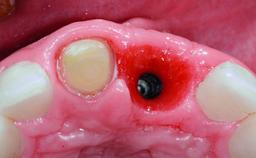

A 49-year-old female patient was referred for implant therapy to replace the upper right central incisor (tooth 11). The tooth had been assessed by an endodontist who diagnosed a vertical fracture of the root. The tooth had a hopeless prognosis and needed to be extracted. The patient was healthy and was not taking any medications. She was allergic to penicillin. The patient had high esthetic demands but her expectations were realistic. The extraoral examination revealed no facial asymmetries. The right temporomandibular joint demonstrated an opening click but was otherwise asymptomatic. The lip line was high with a significant gingival display.

Type of Implants Two-Piece

Attachment Two-Piece

Bone Augmentation Simultaneous|Vertical